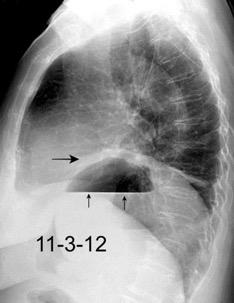

Accidente de tráfico

Rx: Niveles hidroaéreos en hemitórax izquierdo Desviación mediastínica Ausencia de intestino en abdomen. Configuración en reloj de arena del intestino herniado “Tubo nasogástrico”

Furak J et al. Diaphragm and transdiaphragmatic injuries. J Thorac Dis 2019

Diafragma “colgante” (“dangling sign”)

(“Dangling sign”)

TC. Mejor con multicorte. (reconstrucciones).

Asociación: Aire en pared.

Fracturas costal .Rotura esplénica. Neumoperitoneo.

Diafragma discontinúo Herniación de la grasa omental

Desser TS et al.The dangling diaphragm sign: sensitivity and comparison with existing CT signs of blunt traumatic diaphragmatic rupture. Emerg Radiol 2010